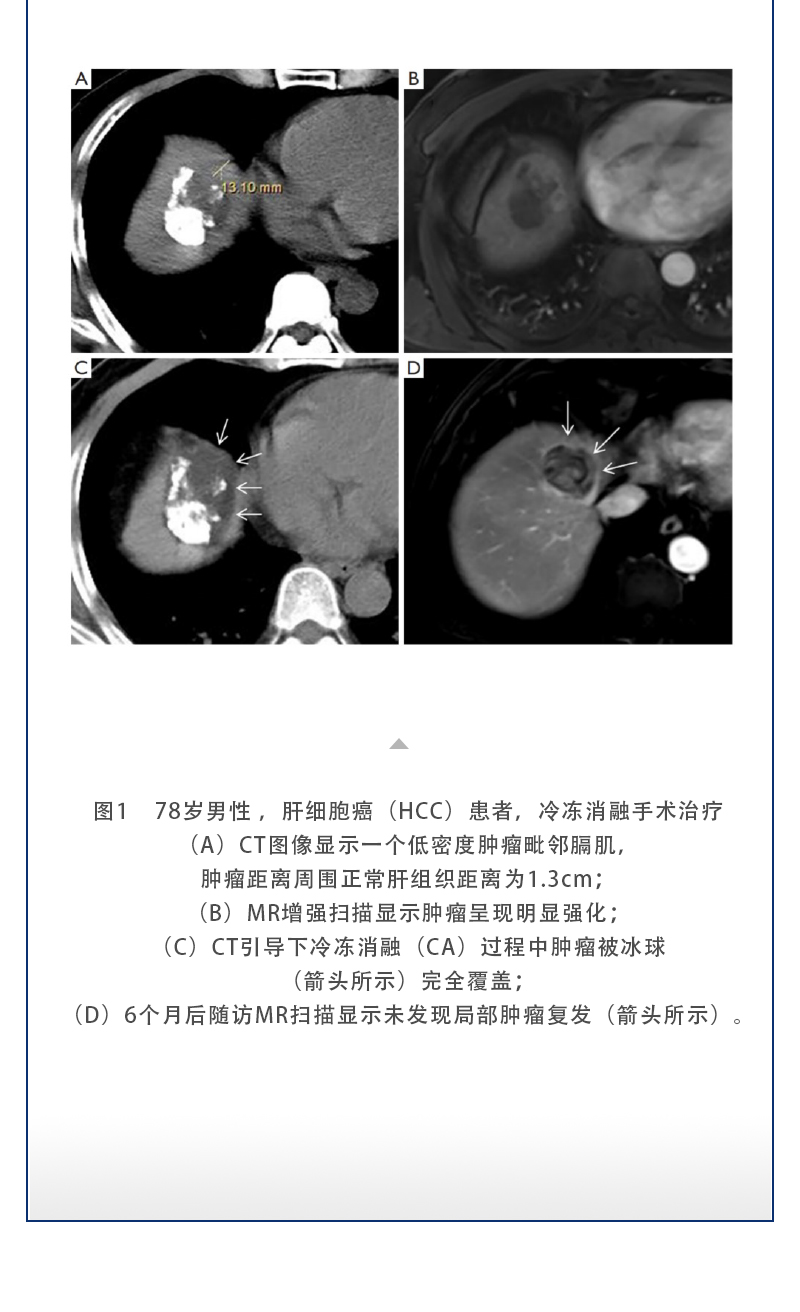

【HYGEA·科研資訊】冷凍消融治療肝癌

發(fā)布時間:2025-09-05 | 作者:海杰亞 | 瀏覽次數(shù):593